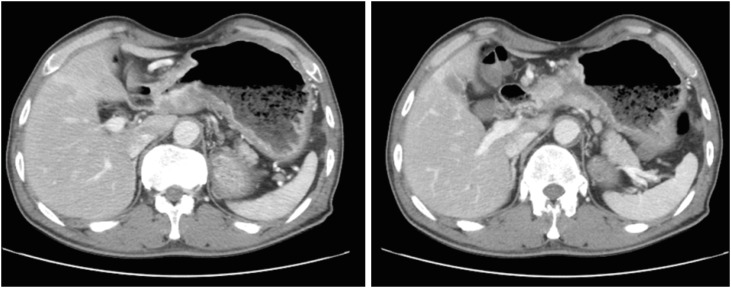

A 57-year-old man was informed regarding a possible diagnosis of gastric cancer at a local clinic on November 15, 2016, based on the results of endoscopic examination previously performed following his complaints of weight loss, abdominal pain, and indigestion. On the same day, the patient visited the department of gastroenterology at a university hospital for endoscopy including biopsy. The tests revealed advanced gastric cancer in the distal antrum (Fig. 1). Abdominal computed tomography (CT) scans subsequently confirmed the presence of cancer and metastasis. The results showed invasion of the entire wall of the antrum with regional lymph node metastasis (Fig. 2). He was diagnosed with stage IIIB gastric cancer (T4N2M0). On December 6, 2016, the patient underwent subtotal gastrectomy with Billroth I anastomosis and cholecystectomy, and was started on chemotherapy. Despite the treatment, he died of gastric cancer on January 9, 2018. Apart from having received treatment for chronic hepatitis B, the patient had never been diagnosed with any disease of the GI tract prior to the gastric cancer diagnosis. During the endoscopy performed on November 15, 2016, he was not tested for H. pylori infection; in addition, he never underwent any tests for H. pylori infection. We were thus unable to determine the presence of H. pylori infection. He had a 1–10 pack-years history of smoking, did not drink, and had no particular relevant family medical history. At the time of his job history survey, the patient was working as a day laborer; his official job history could not therefore be established. We accordingly reviewed his employment insurance records, the National Tax Service (NTS) reports, and his own statements. Based on the combined information, we summarized that the patient had worked as an oxygen cutter at shipbreaking workplaces from 1978 to the 1990s (for approximately 17 years). Furthermore, during the 1990s and 2010s (until 2016), he worked for 7 years at building demolition workplaces as a member of the boiler dismantling crew, and also spent another 14 years in dismantling factories and various thermal power generation plants. Altogether, the patient had presumably worked for about 40 years since 1978 as an oxygen cutter at workplaces that dismantle ships, buildings, boilers, and thermal power plants.

Fig. 2

Patient A: abdominal computed tomography images. Abnormal wall thickening and enhancement in the gastric antrum with regional lymph node enlargement.